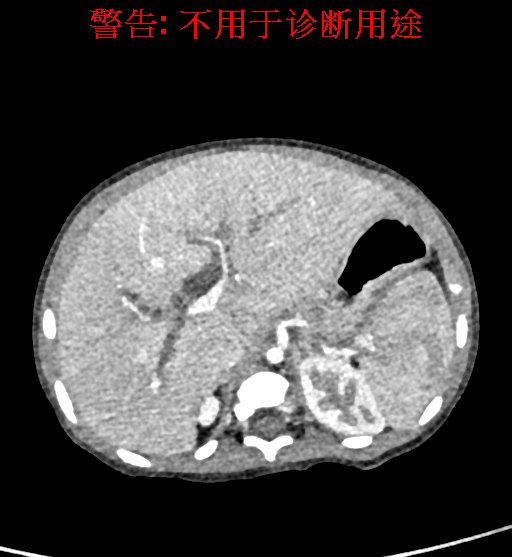

实验室检查: 血常规:WBC 16.16*109/L,NEU2.88*109/L,RBC3.76 1012/L,HB 92g/L, PLT 414*109/L 生化全套:ALT 50.00 U/L, AST 147.00 U/L, ALT/AST 0.34,LDH 367.00 U/L, ALB 36.91g/L, GGT 1297.00 U/L, ALP 1155.00 U/L, BIL-T 138.23 umol/L, BIT-D 97.01 umol/L, TBA 48.40umol/L,ADA 40.00U/L, PAB 121.40mg/L, BUN 1.98 mmol/L, CREA 17.00 umol/L 肝炎全套: 炎症反应标志物:CRP 7.27mg/l 诊疗过程: CT结果输入海信CAS系统后行3D重建及手术规划后,于2018-5-31全麻下行“胆总管囊肿切除+肝总管空肠吻合术”手术治疗: 术前三维重建及手术方案设计: 将0.625mm双源薄层CT资料的静脉期和动脉期Dicom格式文件导入海信CAS系统。 通过调节窗宽窗位调整CT序号,对肝实质,胆囊,下腔静脉,肿瘤,肝动脉、门静脉及肝静脉等进行三维重建;系统自动计算肝脏体积,肝脏体积为648.3ml,通过术前模拟手术,精准判断手术切除范围,进行精密术前规划及讨论后实施手术。 手术步骤: 麻醉成功后,患儿取平卧位,2.5%碘伏消毒手术区皮肤,铺无菌巾单。取右上腹纵口长约5m,切开皮肤、皮下织组,腹直肌前鞘、腹直肌,后鞘和腹膜。探查见:胆总管3×2cm大小,胆囊管迂曲,长约10cm。 剥离、切除胆囊,游离胆总管,将之横断:①近端即肝总管,剪裁后被吻合用;②远端游离切除囊肿内壁,直至胆总管开口于十二指肠处,冲洗后予以结扎缝扎。距treits韧带20cm处横断空肠:①近端与其远端25cm处的空肠侧壁行端侧双层吻合,吻合口通畅;②远端断端封闭,其侧壁剪开,并经横结肠后提至肝门处,与剪裁的肝总管行端侧双层吻合。缝合修补胆囊床及系膜裂孔,肝门部放置橡胶引流管一根。温盐水冲洗腹腔。检查无活动性出血,清点纱布器械无误,依次缝合腹壁各层。手术顺利,麻醉满意,出血不多,未输血,术后病人先进入麻醉恢复室,苏醒后回病房。手术时术者可开启Hisense CAS系统手势控制功能,对肝脏及胆囊解剖结构进行实时、全方观察、评估,起到术中导航作用。 术后病理: 1. (囊肿壁)囊肿性病变,囊壁部分区域衬覆柱状上皮。 2. 慢性胆囊炎。 3. 送检(肝门)淋巴结查见淋巴结1枚,呈反应性增生。 随访情况: 患儿术后2周恢复良好 术前CT检查:动脉期

静脉期

平衡期